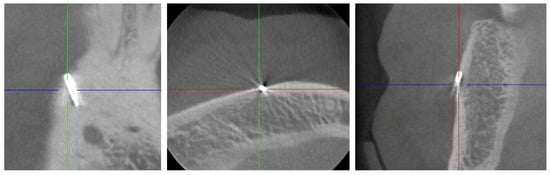

2.2. Digital Volume Tomography (DVT)

For the presurgical planning, a three-dimensional imaging using cone-beam tomography (CBCT) was made (Figure 2), using a MORITA 3D Accuitomo 170 (MORITA Europe, Jordi Röntgentechnik AG, Münchenstein, Switzerland) with a spatial resolution (voxel edge length) of 0.08 mm. The recording time was 17.5 s at 90 kV and 5 mA (pulsed).

Figure 2.

Cone-beam tomography showing the metallic opacity compatible with a broken tip of a periodontal probe. No close relationship to the mental nerve canal or supplying vessels was evident.

An opacity corresponding to the findings described in the OPT, but buccally perforating the cortical bone, was found. The shape, which was typical for a periodontal probe of the type AE P OWB (Michigan O with Williams Markings), led us to suspect that it was a broken periodontal probe tip made of medical steel. A possible differential diagnosis could be excluded with certainty, despite some artefacts.